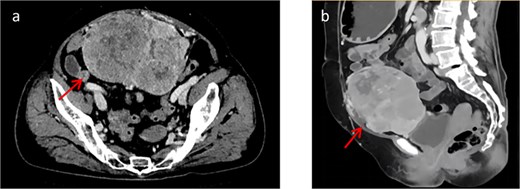

At presentation, contrast-enhanced computed tomography (CT) demonstrated a multiloculated mixed cystic–solid mass in the lower abdomen/pelvis with internal septations, measuring ~13.2 × 9.5 × 12.4 cm (Fig. 1). The lesion was well outlined overall but showed indistinct planes with the adjacent bowel and the anterior bladder wall. Enhancement was heterogeneous, with multiple non-enhancing low-density foci consistent with necrosis. Arterial feeders arose from both external iliac arteries. Magnetic resonance imaging (MRI) confirmed a predominantly solid, lobulated mass (12.3 × 9.6 × 13.7 cm; Fig. 2) with heterogeneous signal (T1 isointense; variable T2 signal) and mildly increased diffusion signal; the minimum ADC was ~0.6 × 10−3 mm2/s. Small cystic/necrotic areas were present, and the tumor appeared locally adherent to the bowel and bladder, favoring a mesenchymal neoplasm.

(a) Shows a cross-sectional view of the pelvic contrast-enhanced CT scan. (b) Shows a sagittal view of the pelvic contrast-enhanced CT scan.